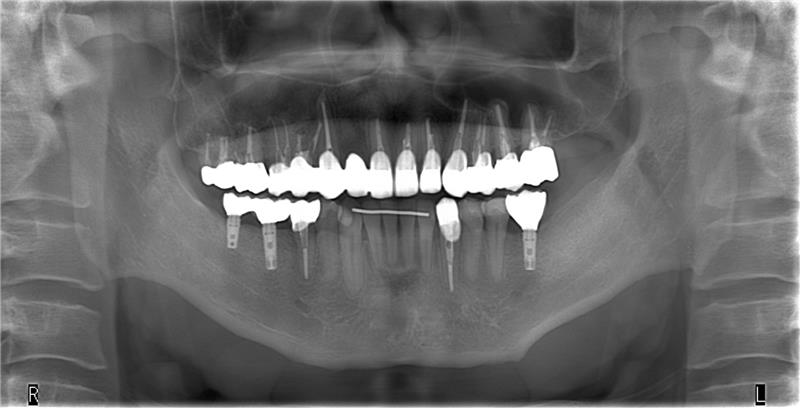

仮のインプラントの上に仮の歯を装着して矯正治療を行い、矯正後に仮のインプラントを外して正規のインプラントを入れました。

このように矯正とインプラントのタイミングを慎重に考えて組み合わせることで、歯並びとかみ合わせと審美、全ての改善を達成できたと考えてます。